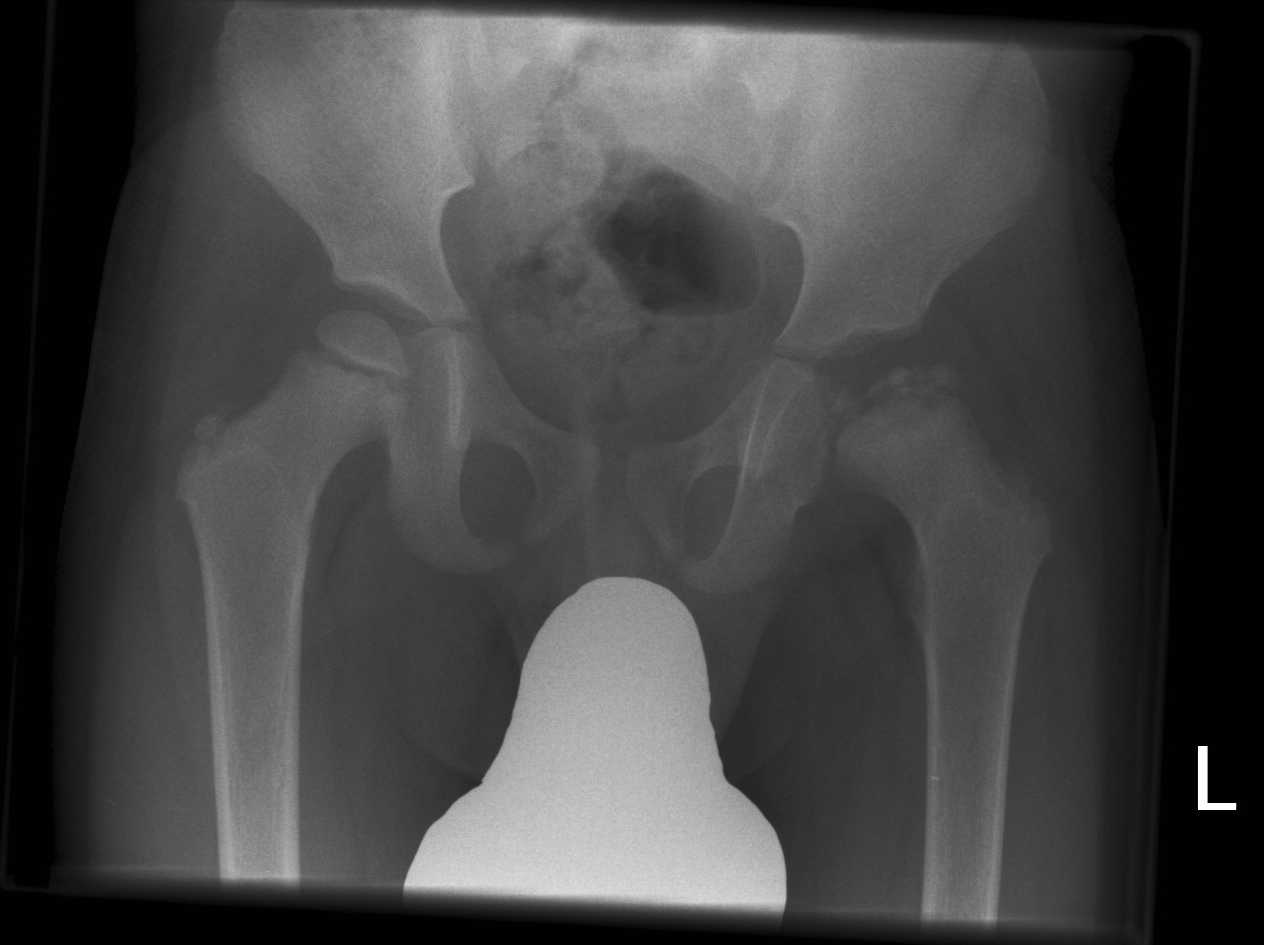

During diagnostic hip arthroscopy, a small and flexible tube with a camera is inserted within the small incisions made. The procedure is performed to determine the condition of the cartilage, ligaments, whether there is loose cartilage material, inflammation, or bone spurs.

Lateral Repair

FAI (Femoroacetabular Impingement)

Femoroacetabular impingement (FAI) is a condition in which extra bone grows along one or both bones that form the hip joint — giving the bones an irregular shape. Because they do not fit together perfectly, the bones rub against each other during movement. Over time this friction can damage the joint, causing pain and limiting activity.

Many FAI problems can be treated with arthroscopic surgery. Arthroscopic procedures are done with small incisions and thin instruments. We clean out any damage to the labrum and articular cartilage.